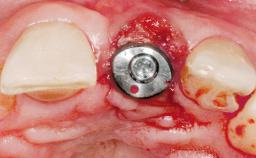

A 42-year-old female patient was referred to our clinic at the School of Dentistry of the University of São Paulo in November 2004, presenting a deficient restoration in the upper left central incisor. The clinical examination revealed no gingival retraction or any signs of gingival inflammation and, therefore, previous periodontal treatment was not considered. The patient presented a high lip line at full smile and a thin tissue biotype. This combination characterized a high-risk situation from an anatomic point of view, which required careful preoperative planning and cautious surgical execution.

Type of Implants One-Piece

Placement Protocol Immediate implant placement

Tooth Site Maxillary incisor or canine

Socket Morphology Single-root socket

Socket Integrity Sufficient, with intact bone walls

Bone Volume Sufficient, with intact walls